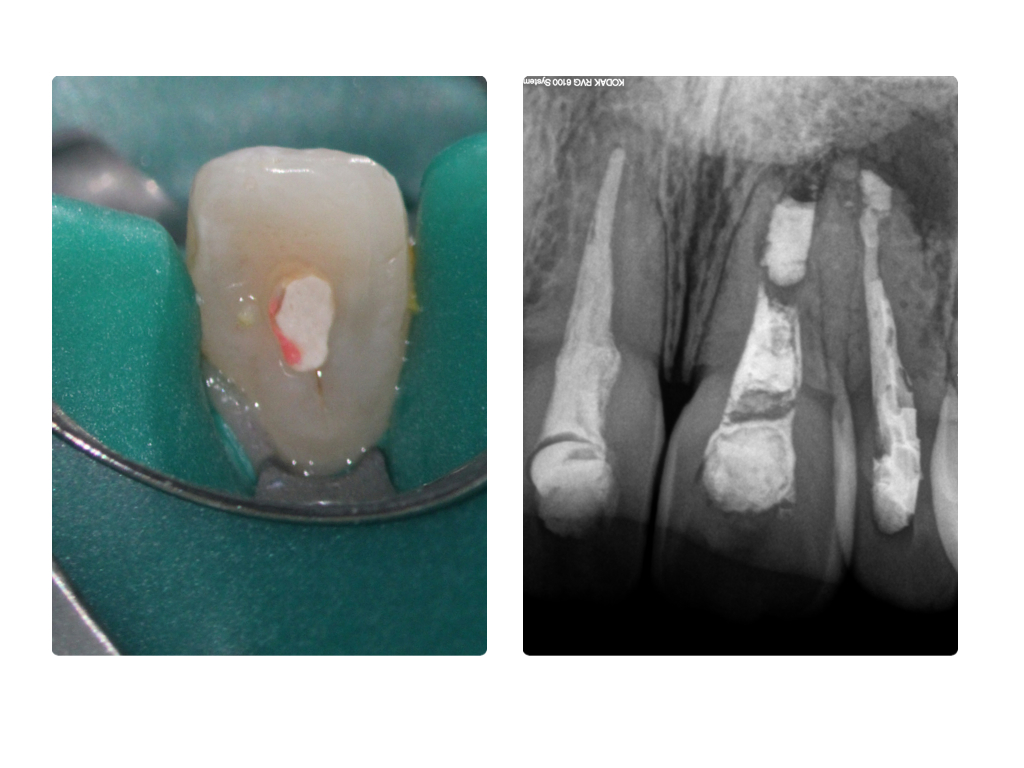

Einbahnstraße WSR (2)

Ausgangssituation